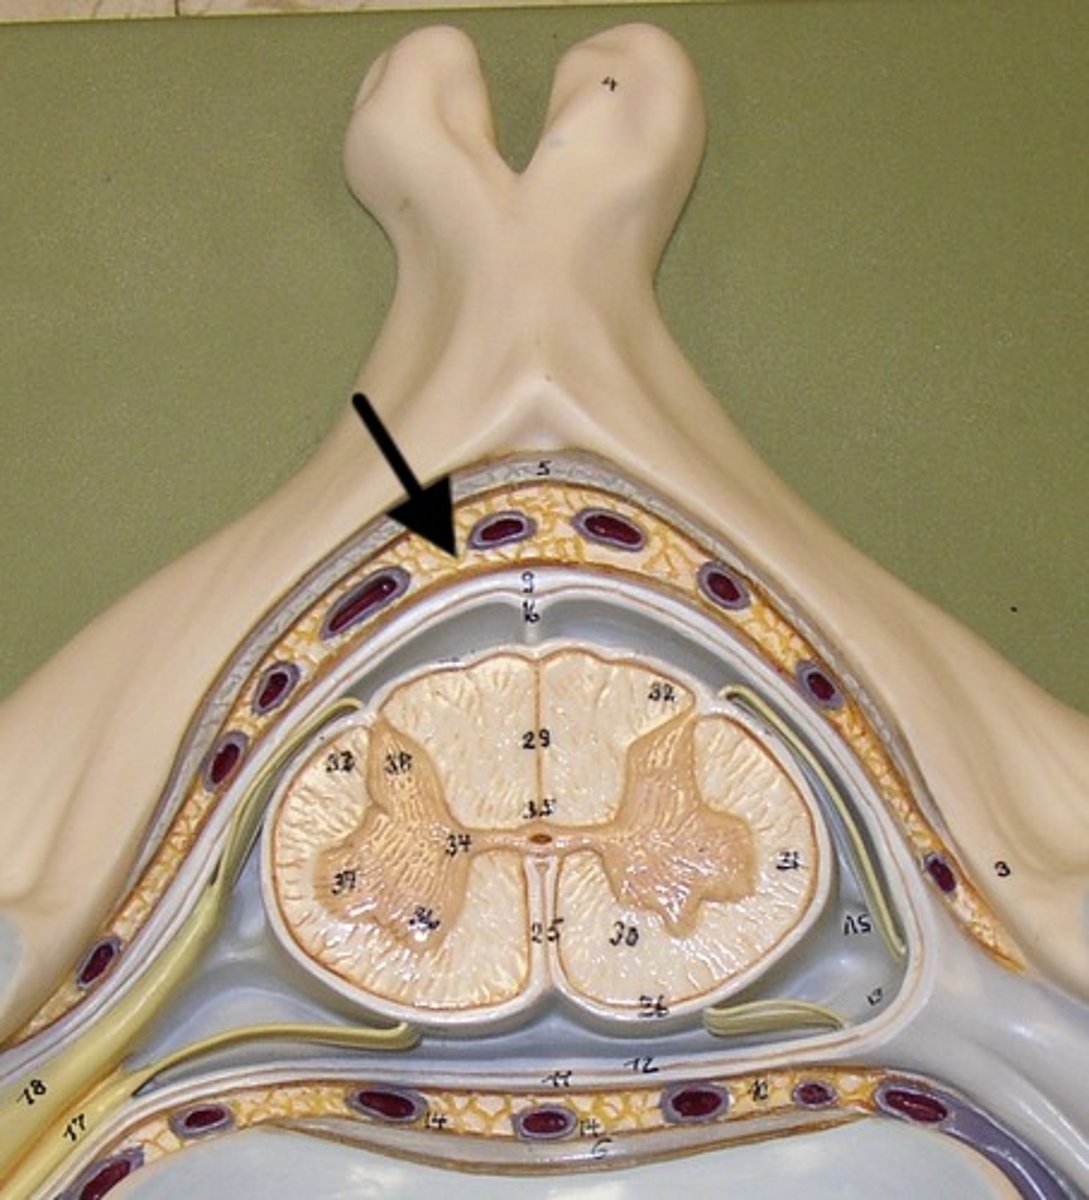

Posterior median sulcus

Anterior Median Fissure

A

B

anterior funiculus

anterior horn

D

Central Canal

E

posterior horn

f

lateral horn

g

posterior funiculus

lateral funiculus